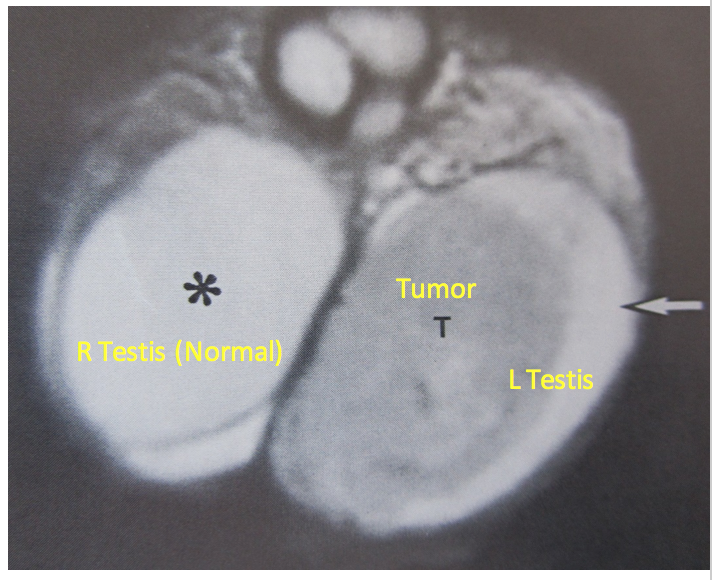

What do the letters represent?

SV: seminal vesicles

P: Prostate

U: Urethra